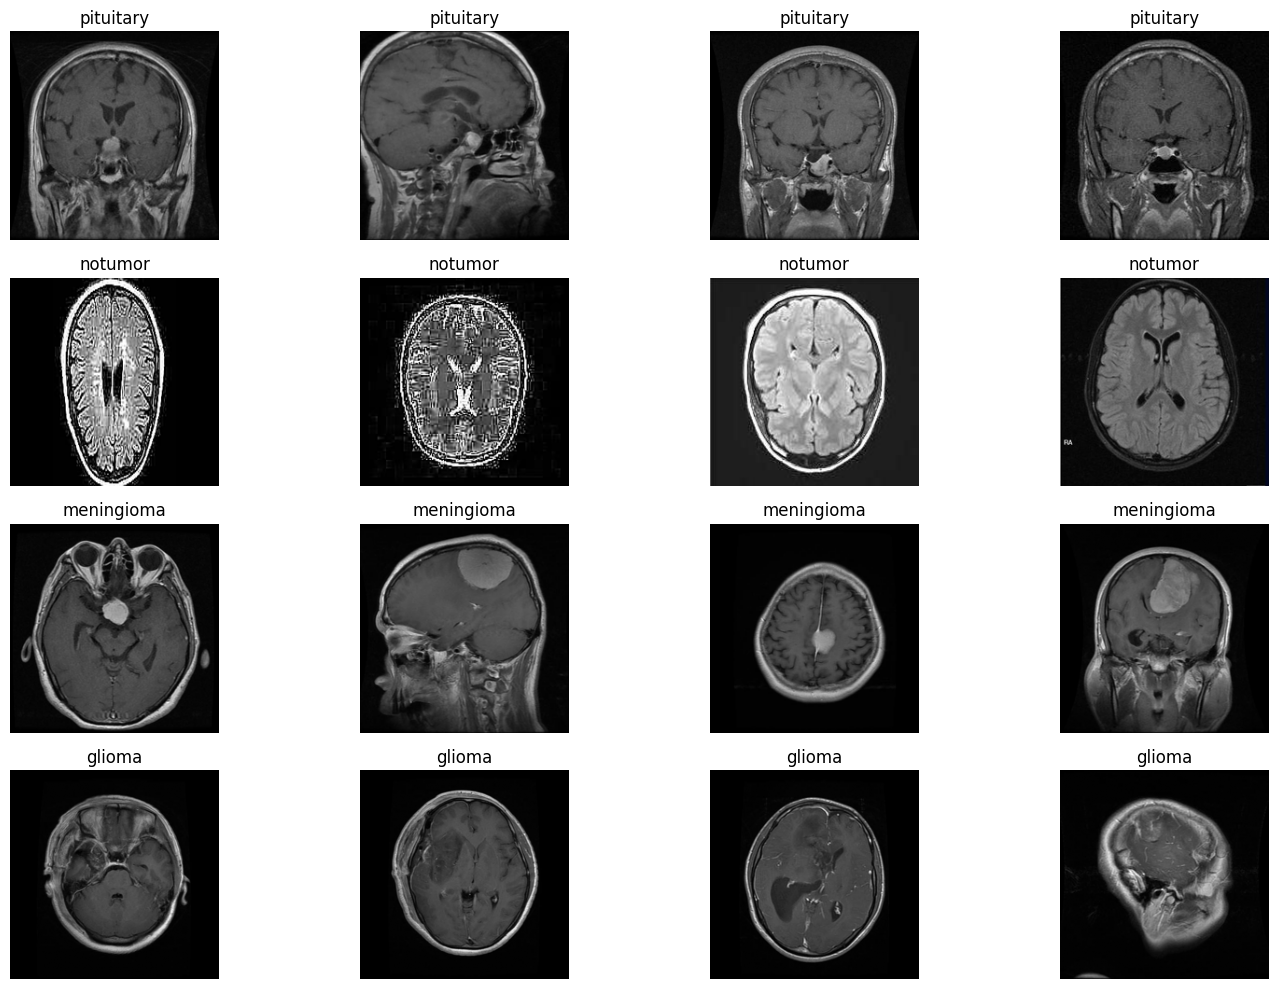

Brain MRI Detection with Interpretability

vit

medical-imaging

attention_rollout

grad-cam